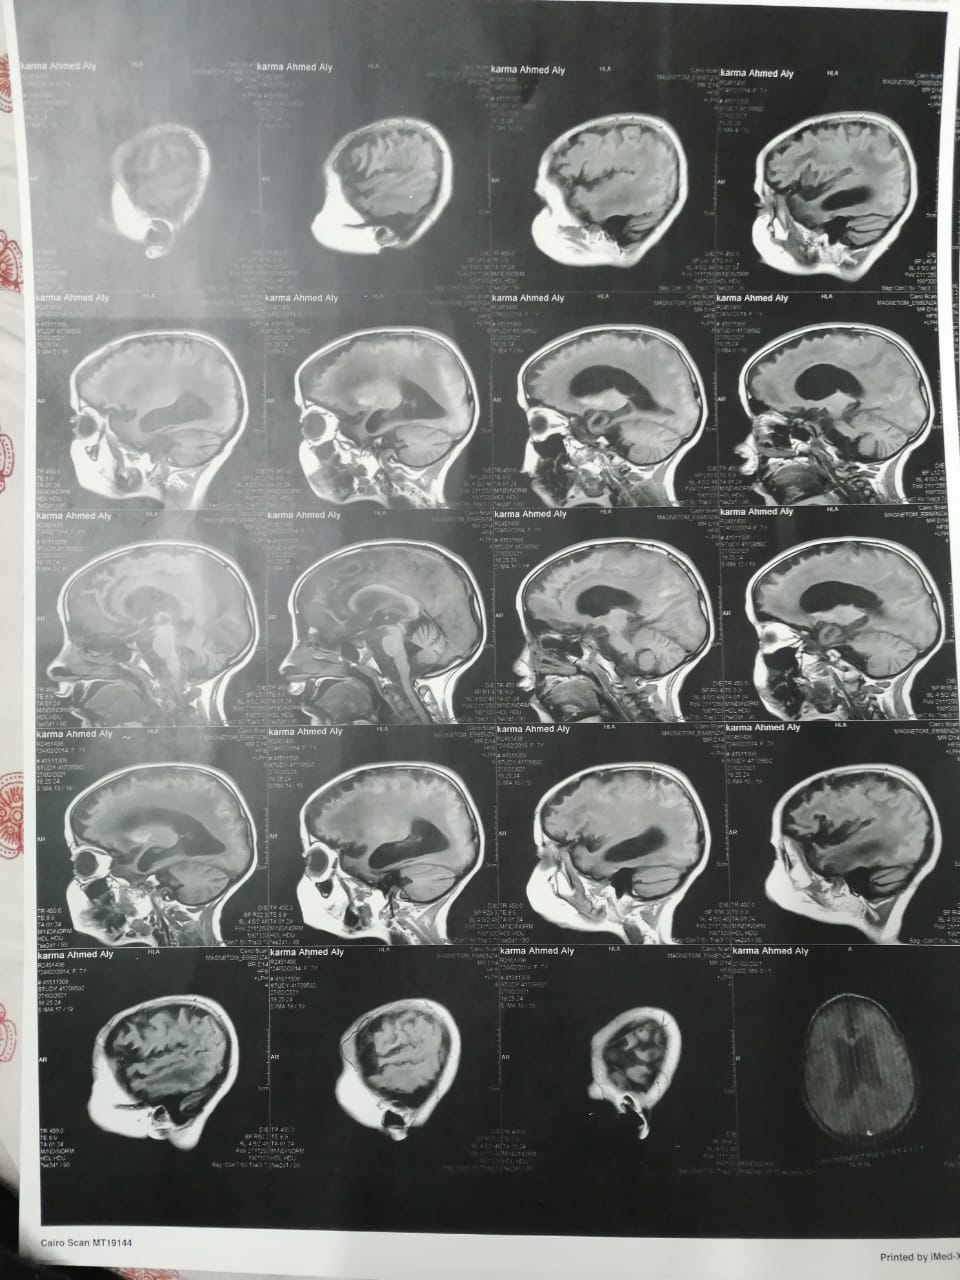

استغاث أحمد علي، بالمسؤولين، لعلاج ابنته صاحبة الـ7 سنوات، المصابة بضمور شديد في المخ، موضحا أن ابنته كانت تعاني من ارتفاع ضغط الشريان الرئوي، وأثناء علاجها أشارت طبيبتها بدواء خاطئ، أدى إلى إصابتها بضمور في المخ.

وأشار إلى أنه بعد خروج كارما من المستشفى تم إجراء فحوصات أخرى عليها، تبينت عدم التطابق بين التقارير الطبية لها بداخل المستشفى والفحوصات الجديدة.

وقال علي: "بنتي جالها ضمور في المخ وفي كل الحواس، بسبب الدوا الغلط، بنعملها علاج طبيعي بيتكلف في الشهر 20 ألف جنيه"، مشددًا": "هي بتفتح عينها بس".